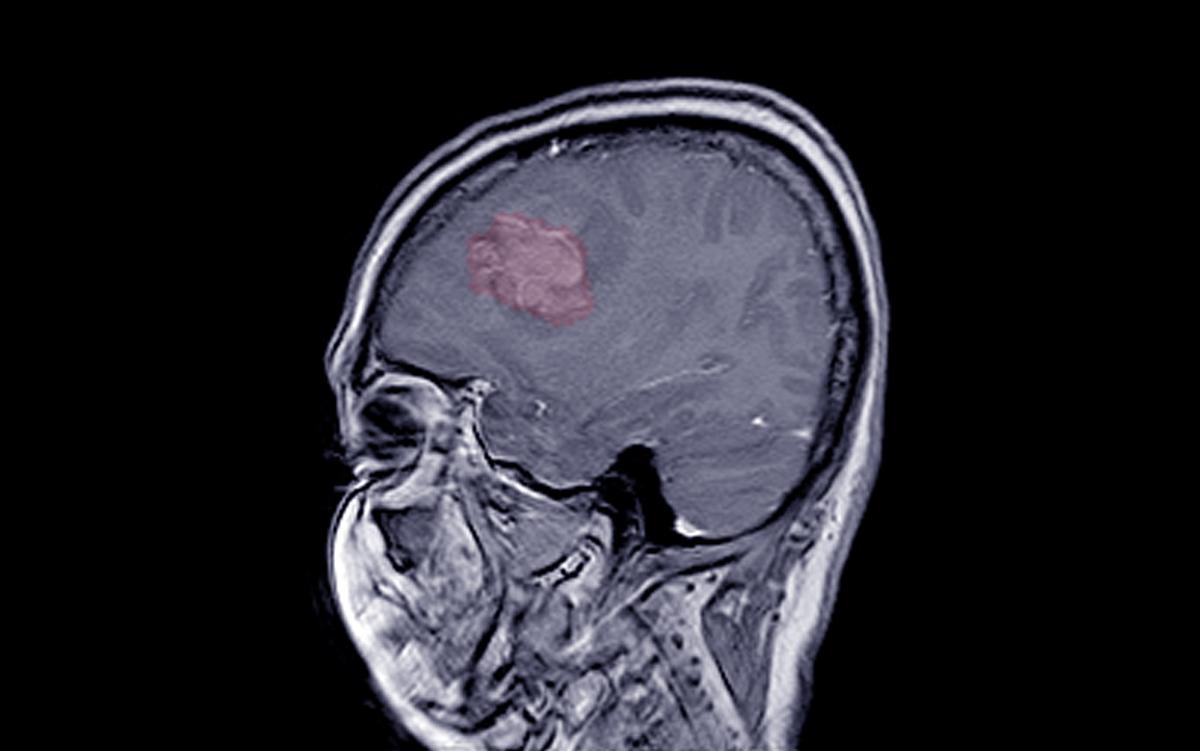

Prolonged use of certain progestogen hormone drugs, including a common injectable contraception, is associated with an increased risk of developing intracranial meningioma tumors.

In a recently published study in The BMJ, French researchers found that medrogestone, promegestone, and injectable medroxyprogesterone acetate—a widely used contraceptive known by the brand name Depo-Provera—increase the risk of intracranial meningiomas requiring surgery.